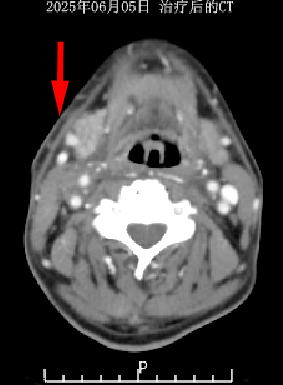

治疗前后对比

经过一段时间的系统治疗,奇迹出现了。患者右颈部巨瘤已基本消失不见,颈部形态与活动功能大幅改善。复查CT影像清晰显示,肿瘤病灶达到完全缓解(CR)标准。从吞咽困难到正常进食,从活动受限到行动自如,这份康复不仅让许先生重获健康体魄,更让他重新燃起了对生活的希望。

治疗前后CT对比